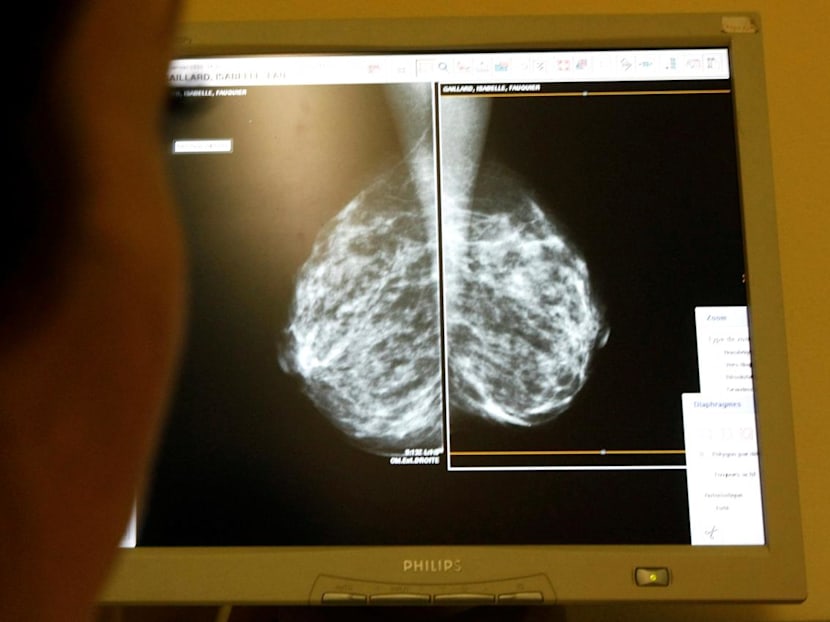

Mdm W’s condition was detected late because she chose not to have her breasts screened regularly, out of an unfounded fear of the potential detrimental effect of radiation exposure from a mammogram.

In reality, the harm from the relatively small dose of radiation encountered in a screening mammogram is often grossly blown-up in people’s minds.

The radiation dose from a mammogram is not very far from the increased comic radiation exposure from a to-and-fro flight to North America.

In short, the benefit of early breast cancer detection through mammography outweighs the potential risk.

Breast cancer in stage 0 and 1 are more commonly detected through mammogram screening. Intuitively, breast cancer in stage 0 or 1 would have a much higher long-term cure rate than disease in in stage 2 or 3.

Unfortunately, less than 40 per cent of Singaporean women aged between 50 and 69 go for a mammogram.